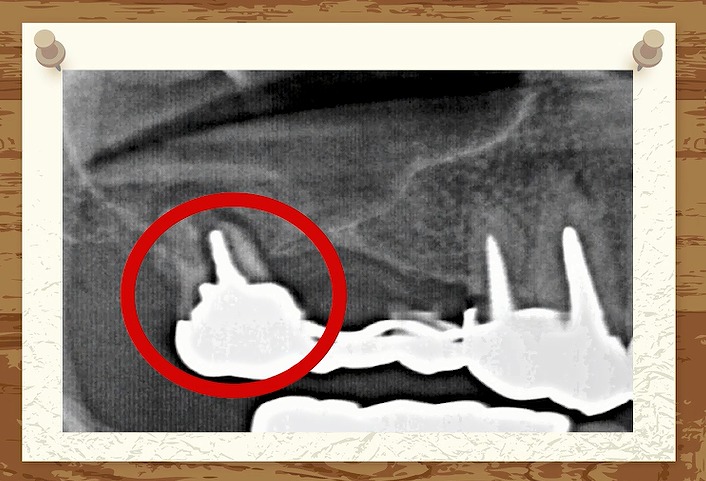

考えただけで

歯がない部分に

ブリッジ治療をしている写真です。

細い歯の方は

歯の根っこが折れました。

こちらは

太い歯

この方は太い歯を土台にした

ブリッジ治療だったので

歯の根っこは折れませんでした

力に耐えられたのですね

ところが

歯を支えている骨

家をイメージすると

柱を支えている地盤

1本1本の柱を支える地盤しか

もともとないわけです。

ブリッジ治療をした場合には

その歯の根っこの周囲の地盤には

本来受ける何倍もの力が実はかかっています。

つまり

地盤沈下が起こってしまうのです